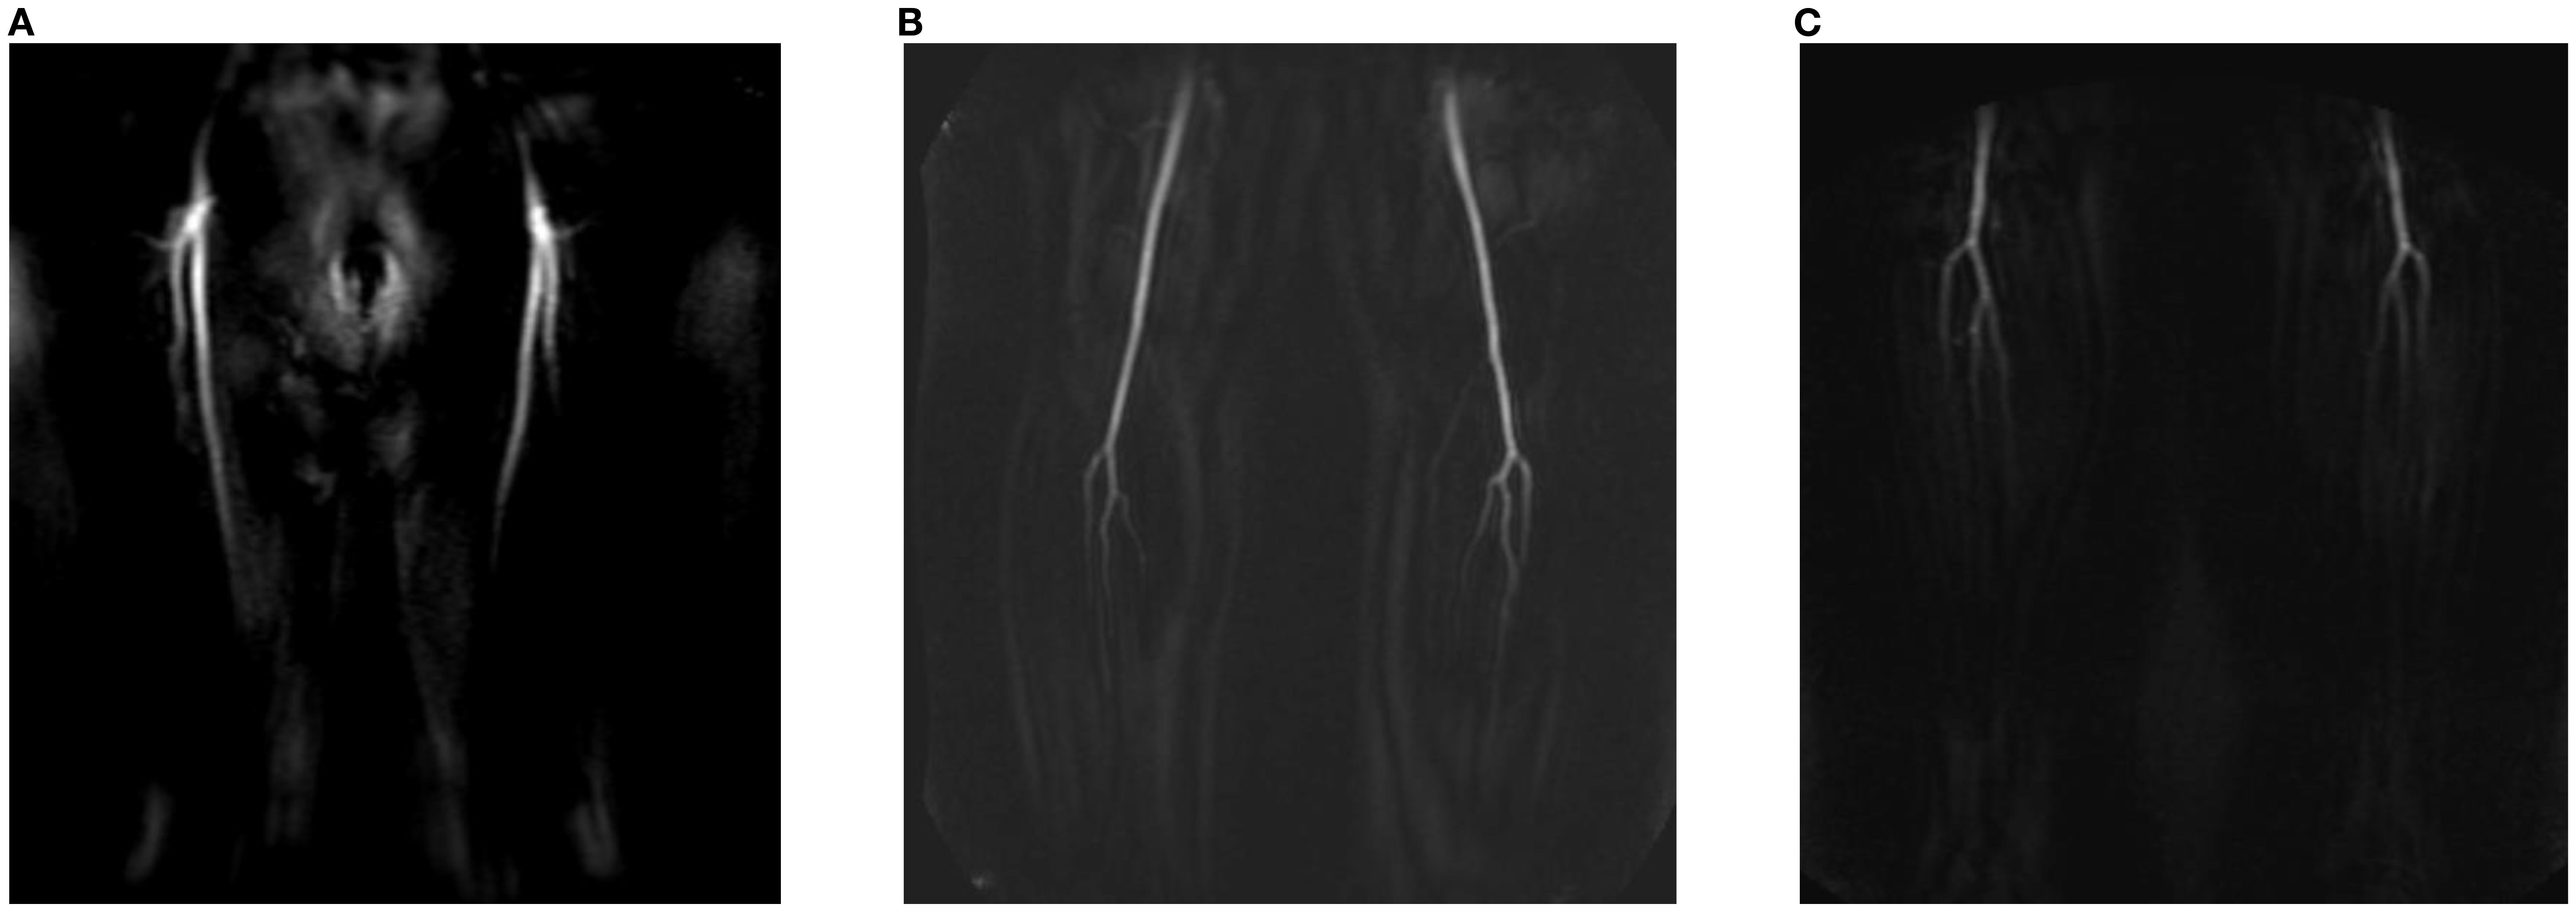

Centra k-space acquisition is used for contrast filling, starting two seconds after fluoroscopic triggering. For optimal perforator filling in the head and neck cancer patient population, the arterial mDIXON scan is triggered when vascular images are seen as shown in Figure 3. For ALT patients, branching of the lateral circumflex femoral artery (LCFA) is visible and contrast fills half of the upper leg. For MSAP and FFF patients, the popliteal trifurcation is visible and contrast fills the upper third of the lower leg. Figure 4 displays examples of arterial mDIXON Maximum Intensity Projection (MIP) images alongside corresponding axial slices, illustrating visible perforators in patients scheduled for surgery with ALT and FFF reconstruction.

Figure 3. View of BOLUSTRAK image when dynamic scan is started for (A) anterolateral thigh flap, (B) medial sural artery perforator flap, (C) fibula free flap.